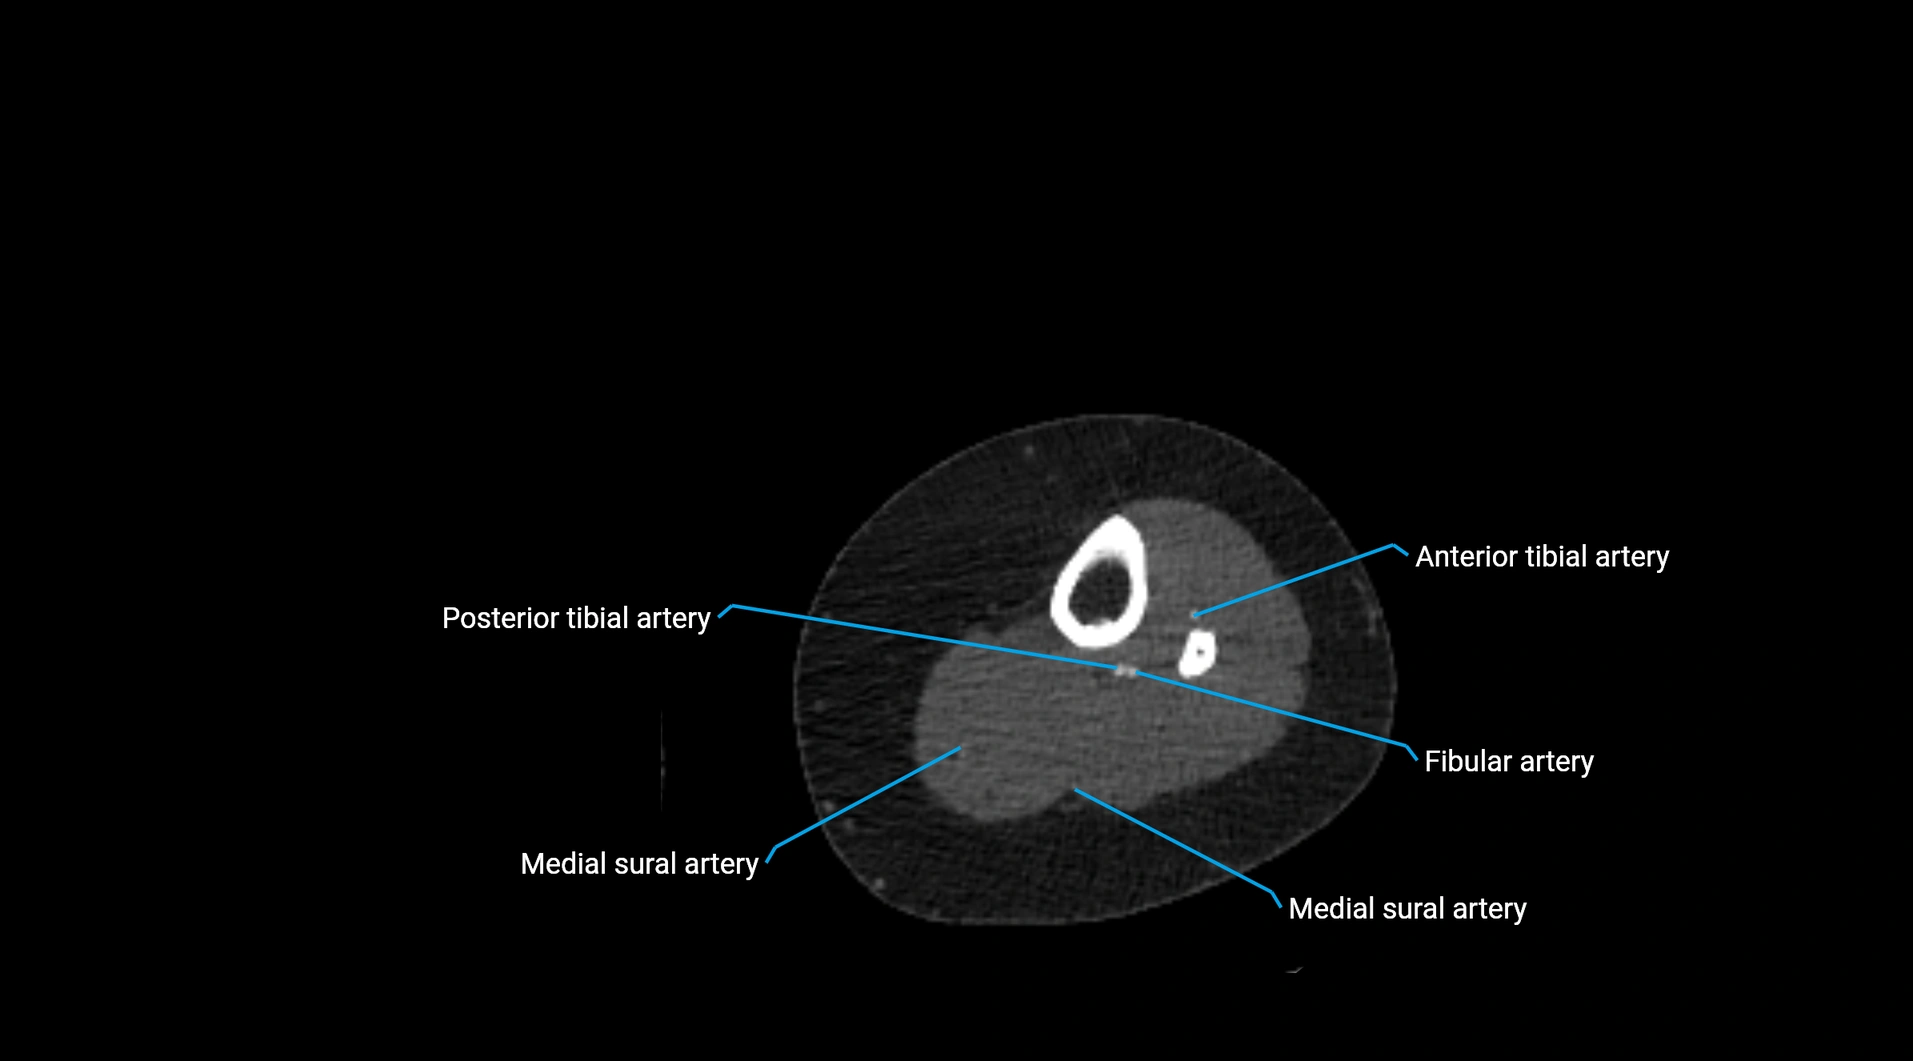

CT Appearance

Non-contrast CT:

• Appears as a tubular soft tissue structure anterior to vertebral bodies

• Calcified atherosclerotic plaques appear as hyperdense foci along the wall

• Useful for screening abdominal aortic aneurysm (AAA) size and mural calcification

Contrast-enhanced CT (CTA):

• Gold standard for abdominal aortic imaging

• Provides excellent detail of lumen, wall, aneurysm, thrombus, and branch vessels

• Multiplanar and 3D reconstructions help in aneurysm measurement, stent graft planning, and dissection evaluation

• Detects acute rupture, traumatic injury, or occlusion with high sensitivity